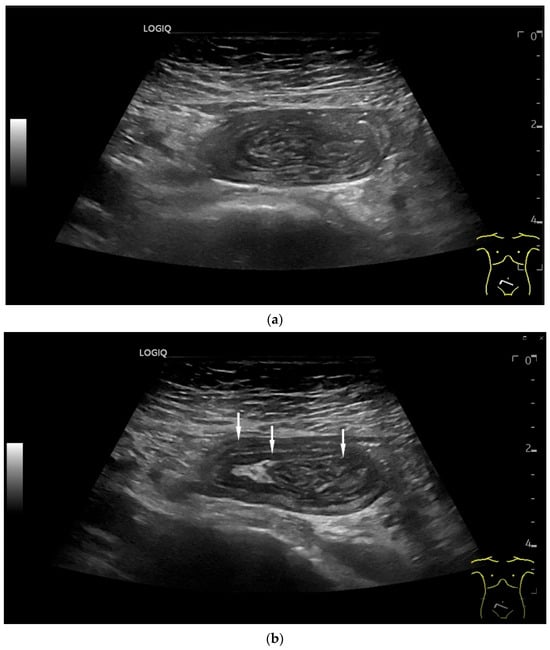

Figure 3.

Intussusception. In the ileum, the intestine is inverted. Instead of the usual five layers, there are many onion-skin-like layers (a). The intestine is folded in on itself several times. The wall is marked with arrows (b).